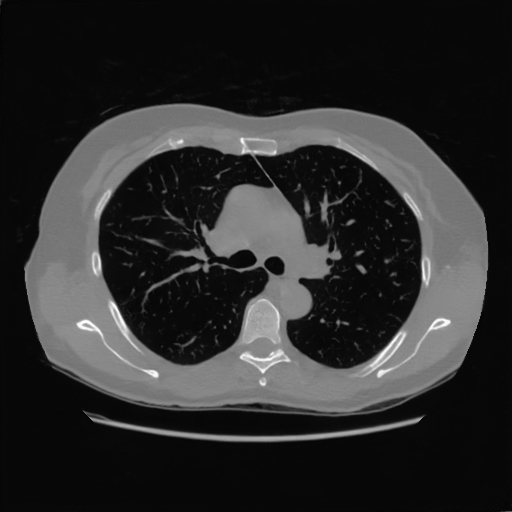

4.4 Limited-Angle CT Reconstruction

To test the proposed framework’s performance on limited-angle reconstruction, we redo the experiment in the above section with the angular range changing from to for parallel-beam geometry and to for fan-beam geometry, one projection per degree. The experiment results are shown in Fig.6. Also, the ground truth and the limited-angle CT reconstruction results of different methods are shown in the row of Fig.7 (parallel-beam, LIDC-IDRI dataset), and Fig.8 (fan-beam, LIDC-IDRI dataset).

16.31dB

20.83dB

13.37dB

16.65dB

13.40dB

16.85dB

22.47dB

14.25dB

22.99dB

19.51dB